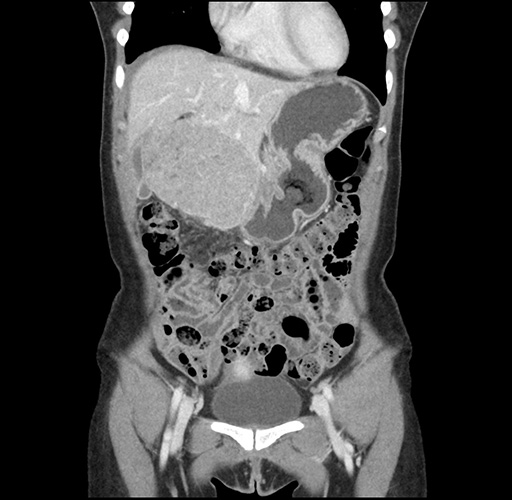

Imaging Analysis

Look through the patient's CT scan to identify any areas of concern for the necessary procedure.

Based on your CT findings, which issue(s) would give reason for "planned slowing down moment(s)" in this case?

Considering a standard left lateral sectionectomy procedure, what step(s) of the operation would you do differently in this case ?